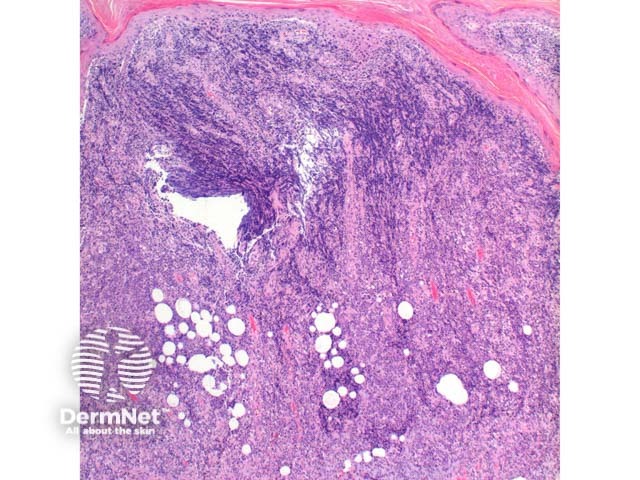

Scanning power view of the histology of primary cutaneous diffuse large B cell lymphoma is of a dense superficial and deep cellular infiltrate (figure 1). Higher power identifies a dense atypical lymphocytic proliferation, which frequently extends into the subcutaneous tissue (figures 2, 3, 4, 5). Areas of crush artefact are common, and while not specific may be a clue to a malignant lymphoid population (figures 2, 3). The lymphocytes are large centroblast-like and immunoblast-like cells with non-cleaved nuclei and prominent nucleoli (figure 6, 7).

Figure 1